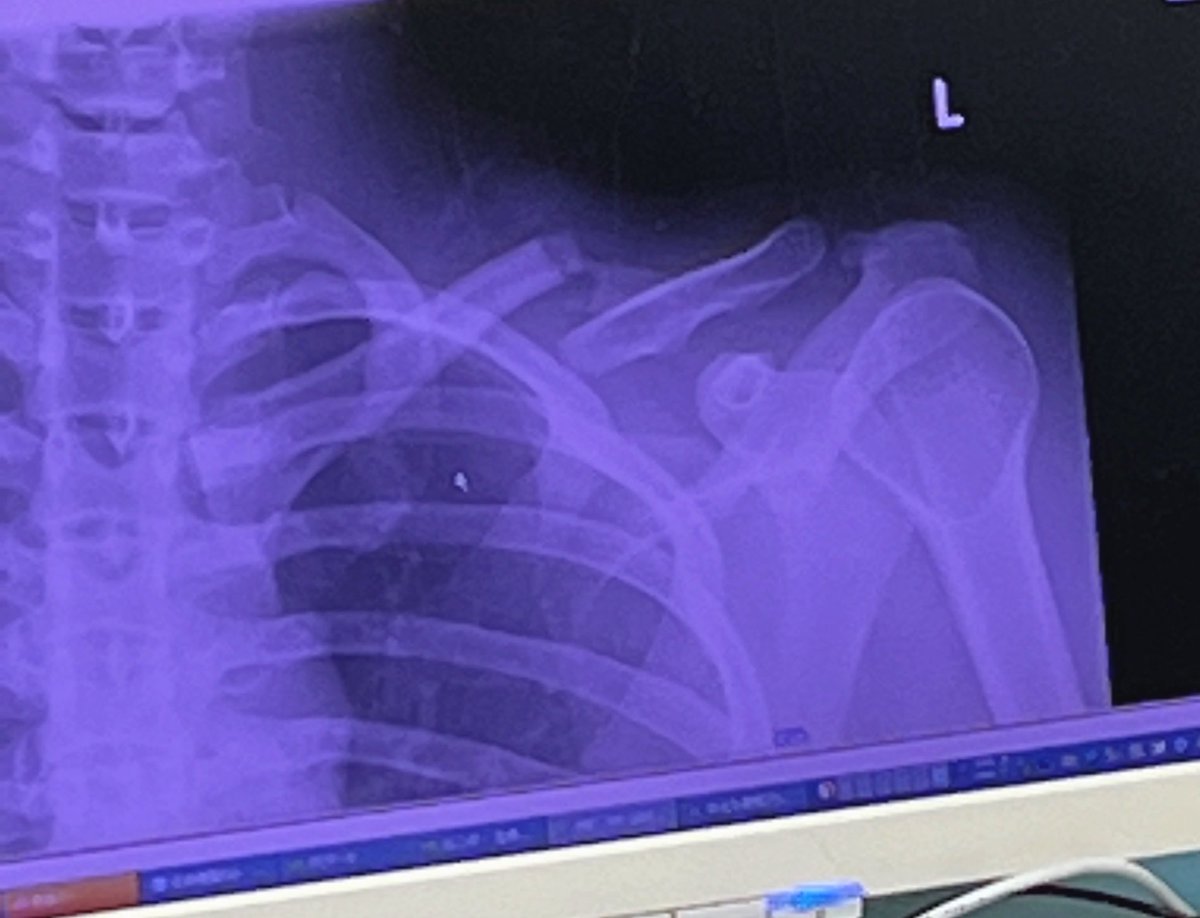

昨日はたくさんのご心配をおかけしたことをお詫び申し上げます。 鎖骨骨折していました。 来週手術予定で 全治3ヶ月の診断を受けました。 しっかり治療して戻って参ります!!